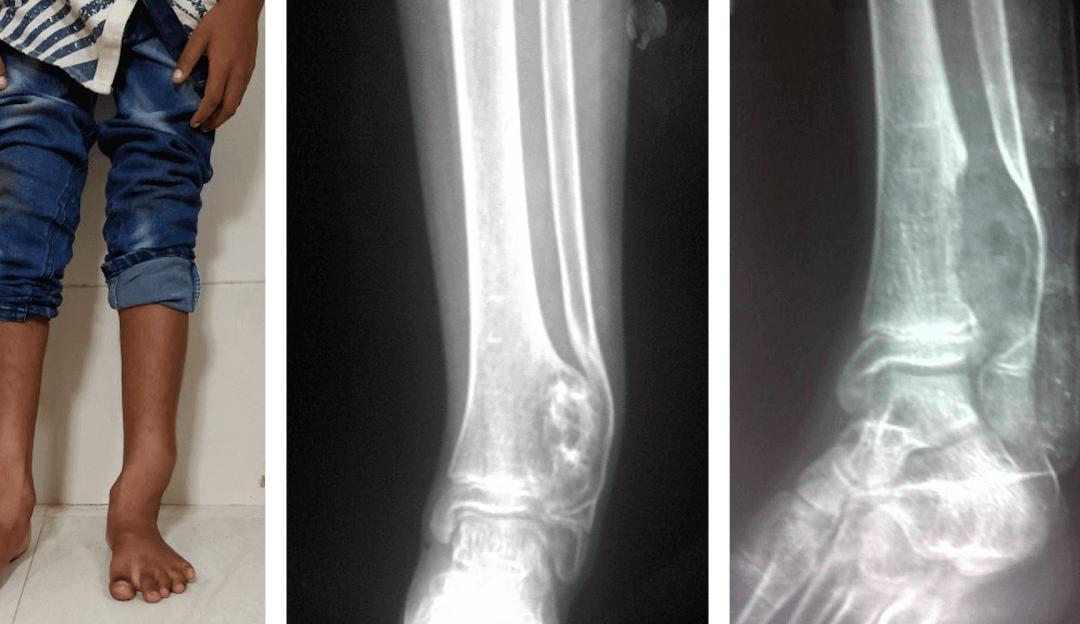

Que.1-What is flatfoot? Ans: The sole of our foot is usually not flat. It has a central arch (Figure 1). Flatfoot is extremely common in young children (1 to 5 years age). Majority of these children develop normal arches as they grow up. In flatfoot, the arch is...